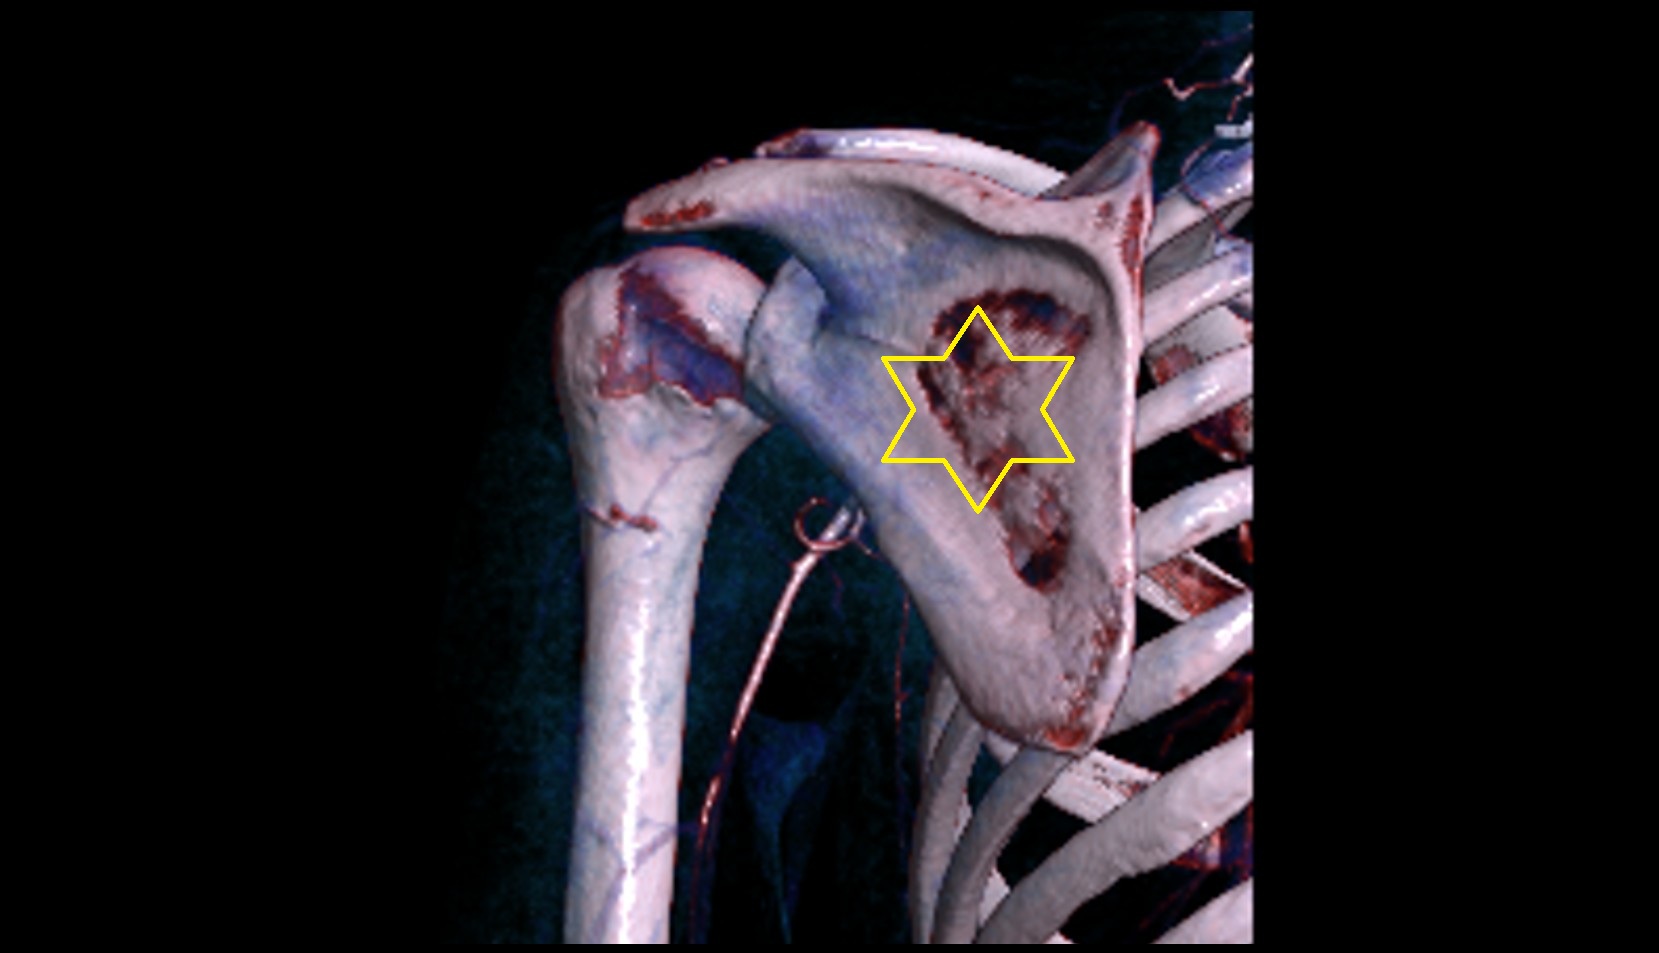

- Glenoid fossa

- Glenoid process of scapula

- Spine of scapula

- Acromion process of scapula

- Coracoid process of scapula

- Scapular body

- Shoulder joint (glenohumeral joint)

- Acromioclavicular joint

- Humerus

- Head of humerus